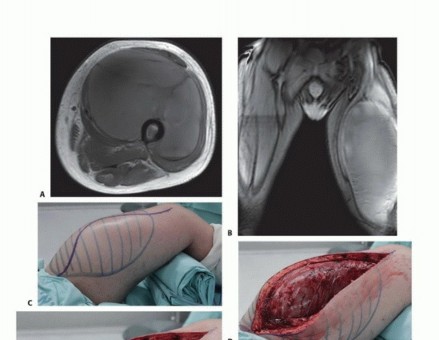

يتم إجراء شق جلدي طولي فوق كتلة الورم مباشرة، ويشمل موقع الخزعة. يجب استئصال كتلة الورم بالكامل مع 1 سم من الأنسجة السليمة المحيطة. بالنسبة للأورام التي تؤثر على العضلة المتسعة الإنسية، أو المتسعة الوحشية، أو المستقيمة الفخذية، فإن الهوامش السطحية هي الجلد والأنسجة تحت الجلد، وقد تشمل الهوامش العميقة جزءًا من العضلة المتسعة الوسطى. أما الهوامش السطحية للأورام التي تؤثر على العضلة المتسعة الوسطى فقد تشمل جزءًا من إحدى العضلات المتسعة أو المستقيمة الفخذية. إذا كان السطح العميق للورم قريبًا من العظم، يجب تقشير السمحاق واستئصاله، وإزالة القشرة السطحية باستخدام مثقاب عالي السرعة (Midas).

الاستئصال الجزئي أو الكلي للعضلة الرباعية

يتم إجراء شق طولي في خط الوسط يمتد من الشوكة الحرقفية الأمامية السفلية إلى الرضفة. يجب أن يكون الشق بيضاويًا ويشمل موقع الخزعة بشكل واسع. إذا أظهر الفحص السريري أو التصوير أن الورم يتعدى على الرضفة، فيجب أيضًا استئصال هذا العظم ووتره. إذا نشأت هذه الحالة السريرية، يجب متابعة الشق فوق الركبة إلى حدبة الظنبوب.

تُصنع رفرفات تتكون من الجلد والأنسجة تحت الجلد فوق اللفافة العريضة مباشرة. تمتد هذه الرفرفات إلى مجموعة العضلات المقربة إنسيًا وإلى المدور الكبير والعضلات القابضة وحشيًا. يتم تقسيم الوريد الصافن عند دخوله الحفرة البيضاوية. يتم الكشف عن الرباط الأربي والمثلث الفخذي، مما يكشف عن الشريان والوريد الفخذي المشتركين والعصب الفخذي.